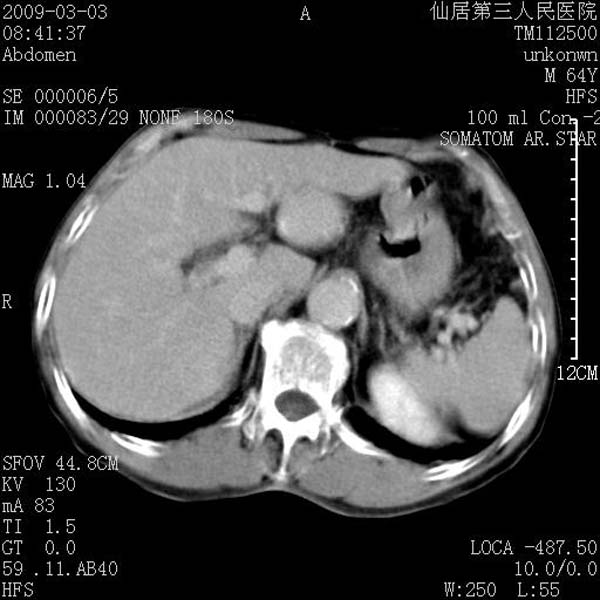

标题: CT18469:男性,64y,体检B超示肝脏低回声肿块,有胃溃疡手术 [打印本页]

患者,男性,64y,体检b超示肝脏低回声肿块,有胃溃疡手术史。

考虑----胃肠道间质瘤可能性大

从平扫及增强的特点来看,支持肝脏腺瘤并出血。

考虑胃间质瘤可能性大。

胃肠道间质瘤!

ct值呢?感觉没强化,象囊性。

考虑肝静脉韧带裂区良性占位性病变(囊肿?)。

考虑肝囊肿并出血可能性大.

考虑高密度囊肿可能性大